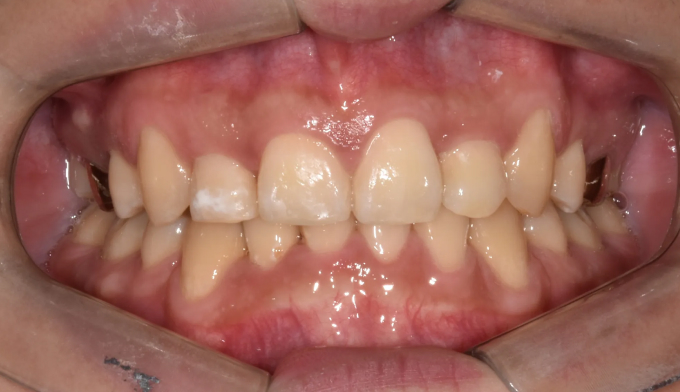

덧니

필요한 공간이 많지 않아도, 입이 많이 나오지 않아도 발치교정을 해야하는 경우들이 종종 있습니다.

비발치교정시 주로 악궁확장이나 치아삭제, 또는 치아 후방이동을 통해 공간을 확보하는데 기존의 악궁이 충분히 넓거나 치아크기가 작은경우, 또는 사랑니가 너무 깊숙히 있어서 발치하기 어려운 경우에는 어쩔 수 없이 작은어금니 발치를 통해 공간을 확보합니다.

교정기간은 총 22개월입니다.

앞니의 길이가 좌우 다르게 보이는 이유는 기존 잇몸의 길이 차이 때문입니다. 이는 잇몸 성형을 통해 개선 가능합니다만 해당 환자처럼 원치 않은 경우에는 안해도 큰 문제는 없습니다.